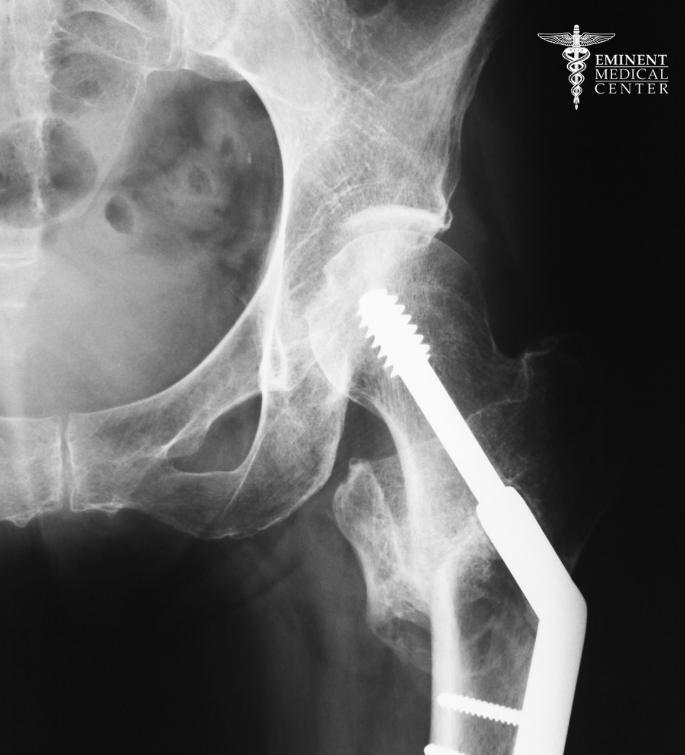

Intertrochanteric Fracture Surgery

Intertrochanteric fractures occur between the greater and lesser trochanters, the bony projections on the upper portion of the femur. These types of hip fractures often result from falls in older adults and can significantly affect the stability of the hip joint.

Common treatment includes internal fixation using a metal rod or intramedullary nail to stabilize the broken bone and allow it to heal properly. Our surgeons work to manage pain, prevent blood clots, and minimize blood loss during surgery while helping patients start physical therapy as soon as possible. Early mobility is essential to avoid complications such as bed sores and to support the healing process.

Subtrochanteric Fracture Repair

Subtrochanteric fractures affect the upper part of the femur just below the lesser trochanter. These fractures are often complex and may occur in both older and younger patients, especially those with underlying health conditions or high-impact injuries.

Because the bone in this region can be more difficult to stabilize, surgical repair typically involves using a long metal rod or intramedullary nail that spans the fracture site. This approach helps support the hip bone while the fracture heals, allowing patients to begin weight-bearing activity earlier.